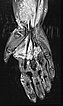

Die koronare, T2-gewichtete, fettunterdrückte Sequenz einer MRT mit Darstellung des rechten Ober- und Unterarms zeigt eine doch deutlich größere Ausdehnung der Malformation als rein klinisch vermutet.

Die Ausdehnung ist vorwiegend subfaszial in der Tiefe der Muskulatur des Ober- und Unterarms. Die Signalgebung ist stark hyperintens, somit sicher eine Slow-flow-Malformation (venös oder lymphatisch).